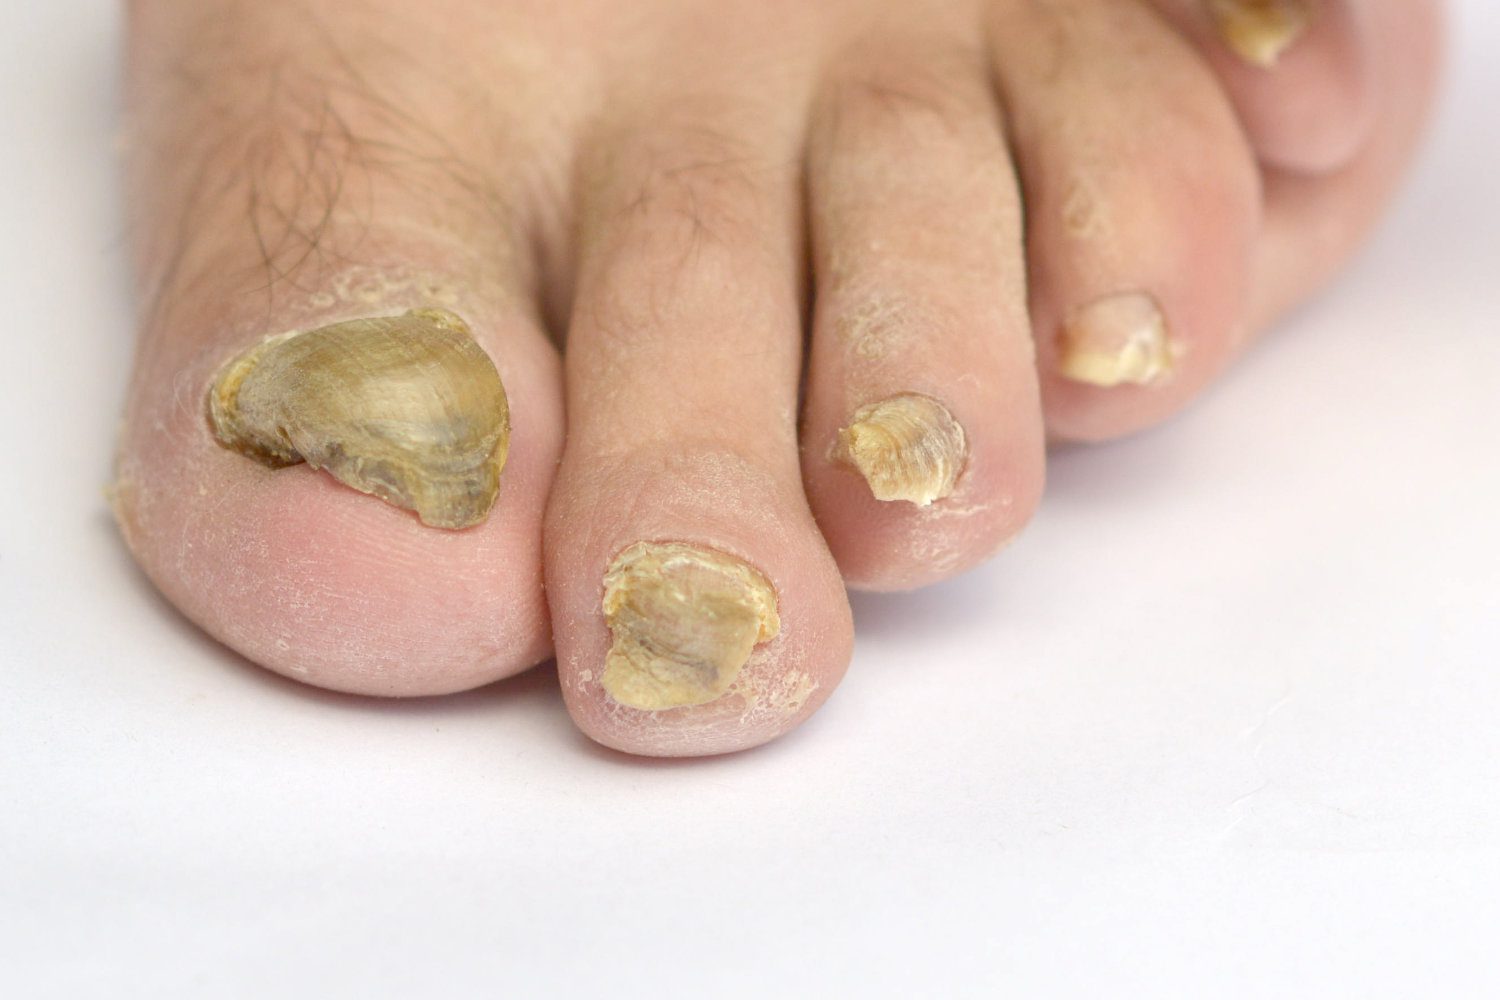

Onychomycosis

A fungal nail infection, referred to in medical terms as onychomycosis, occurs when fungi, a kind of microorganism ...